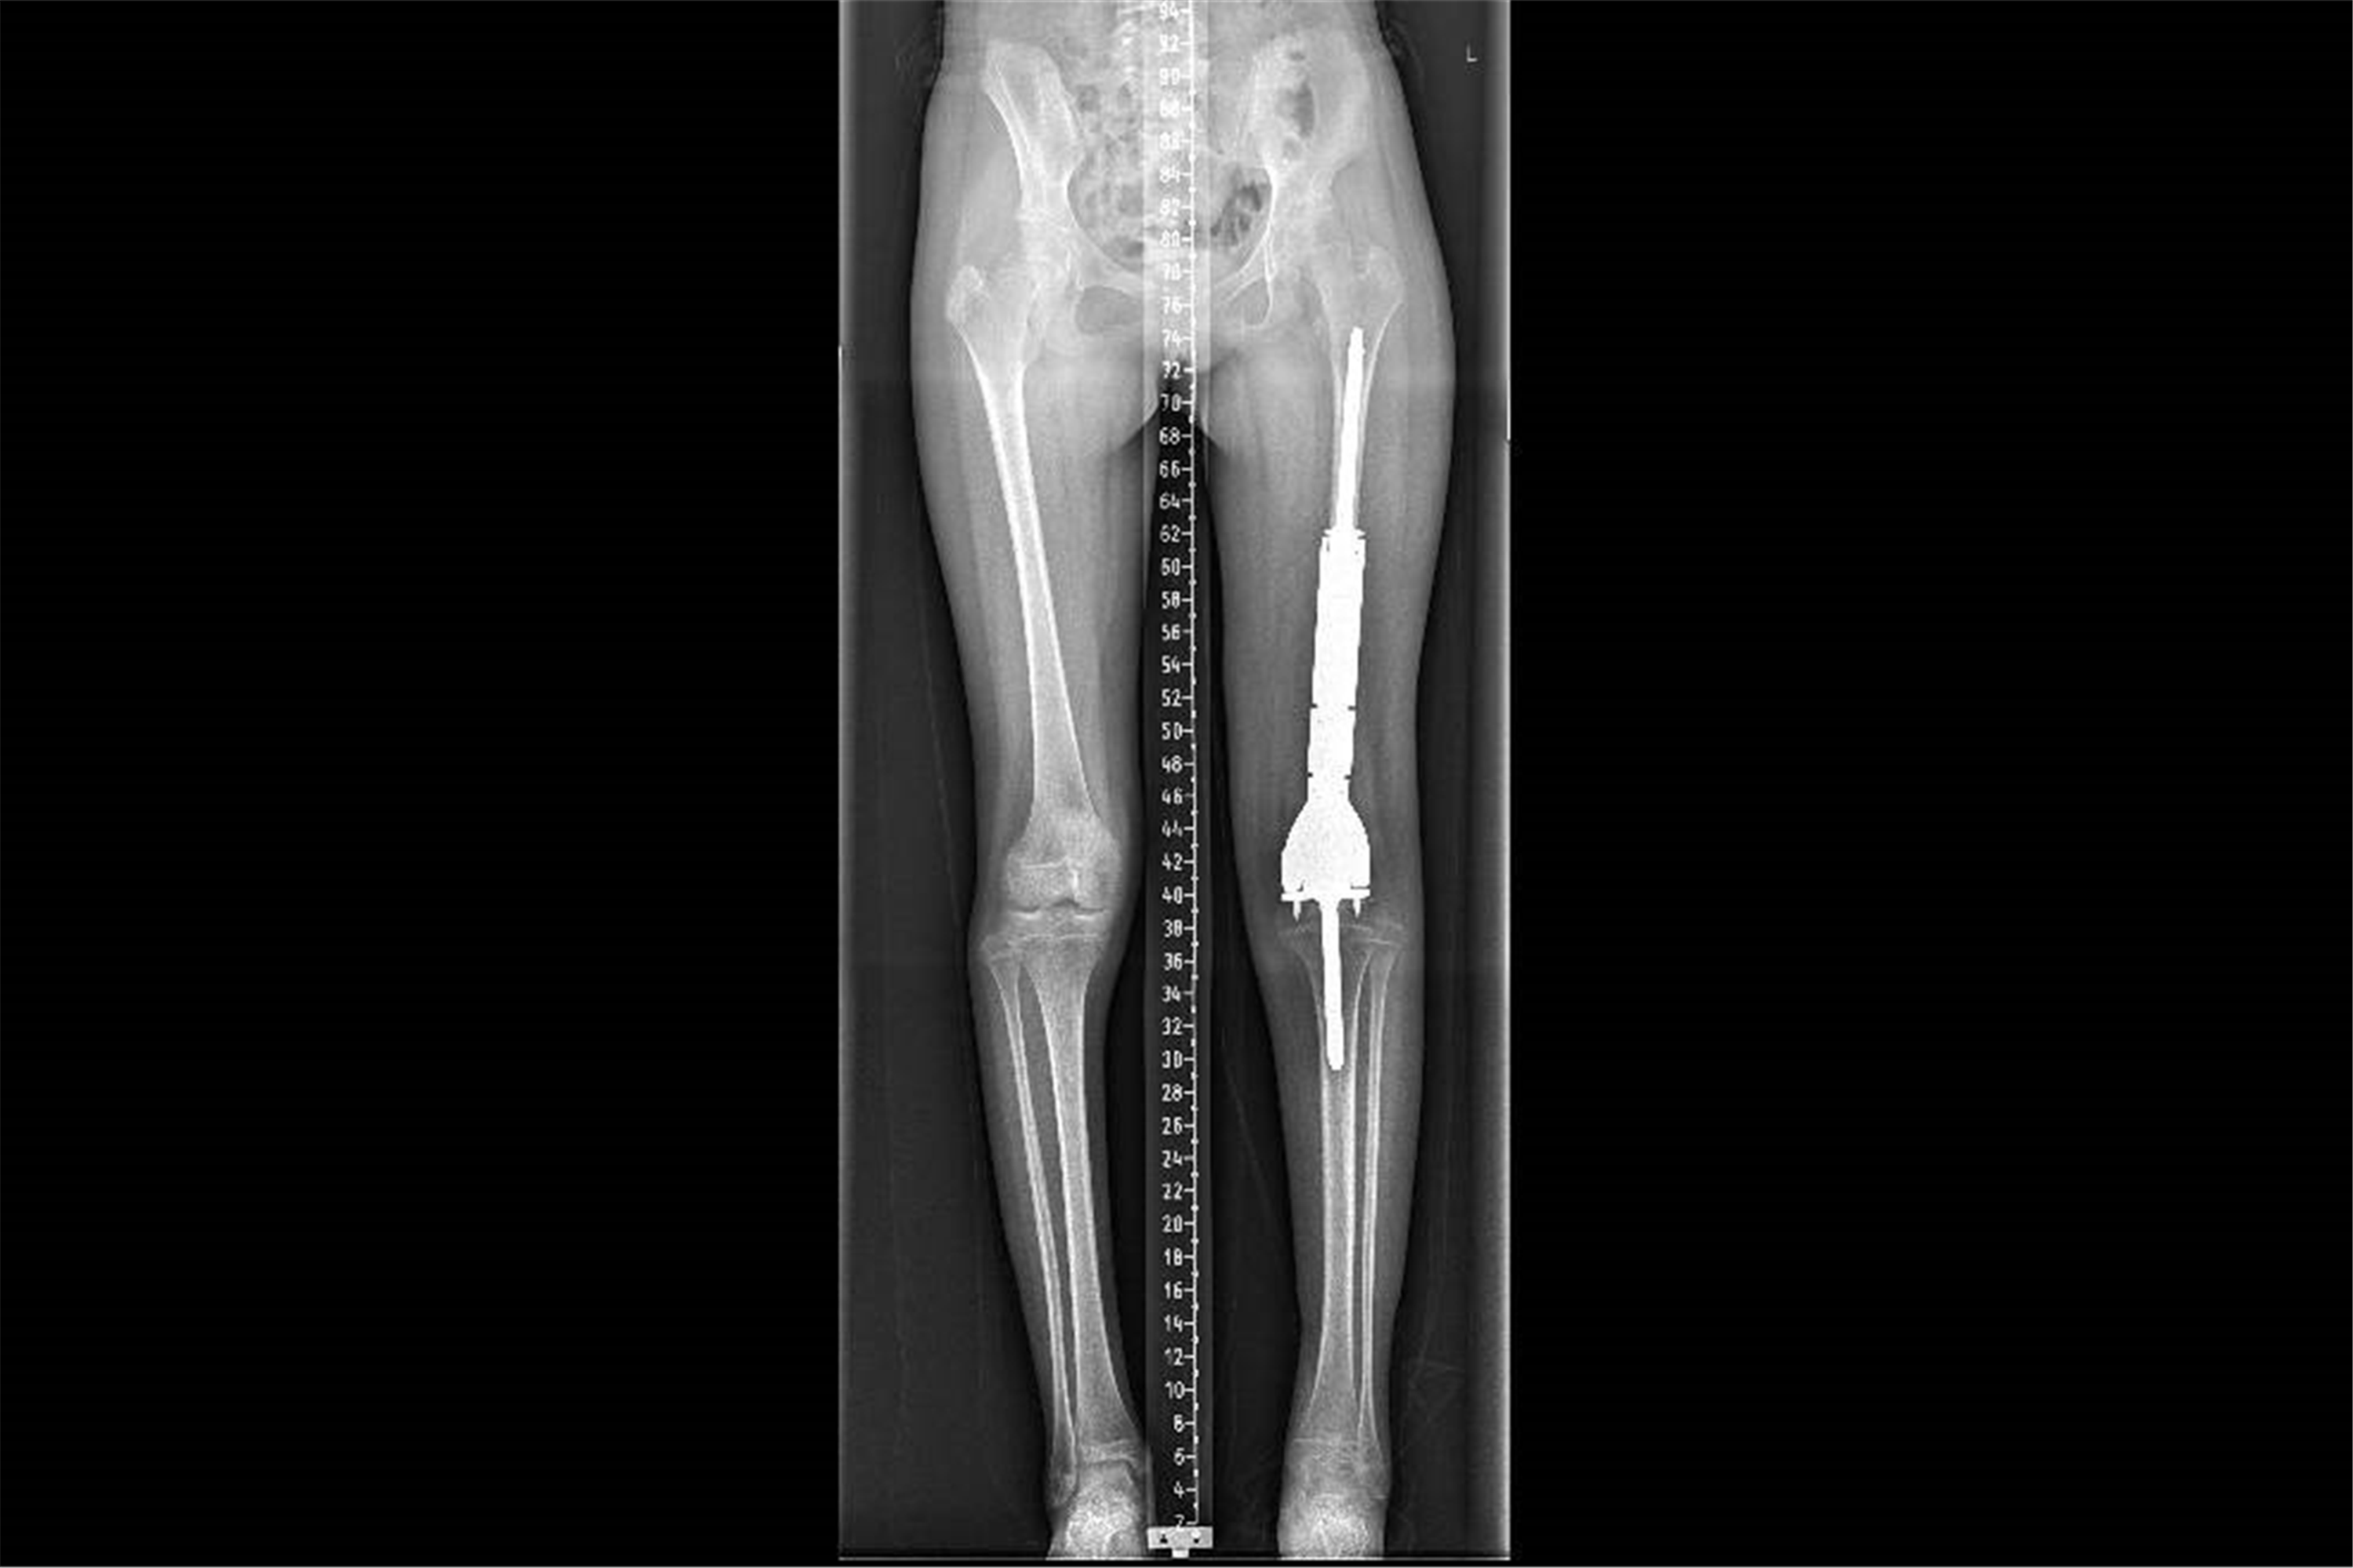

这是小鱼的术后X线影像。

3D打印+可延长假体,精准重建护航未来成长

术后仅两周,小鱼便可在支具辅助下尝试负重行走。接下来,他还将完成后续化疗及系统性康复训练,逐步恢复肢体功能。